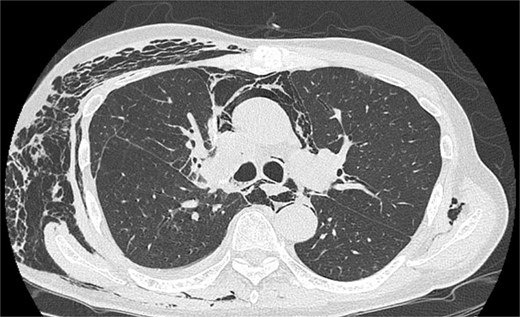

On POD 6, SE developed and spread to the chest, neck, and face. CT demonstrated remarkable mediastinal and SE with minimal lung collapse (Fig. 2; Video 2). Therefore, a chest tube was inserted, but minimal AL occurred from the chest tube, and the emphysema worsened. On POD 11, we performed thoracoscopic exploration and therapeutic intervention. Dense adhesion was confirmed between the staples on the interlobular plane and the dissected upper mediastinum. These were released, revealing the previous pleural tear. No other causative factors were observed. CT and operative findings suggested late-onset AL into the dissected mediastinum through dense adhesions. A leak test under positive pressure of up to 20 cmH2O revealed no AL from the pleural tear. The tear was sealed using a PGA sheet and fibrin glue, and 130 ml of autologous blood was injected into the pleural space to seal the dissected mediastinum and prevent air inflow (Video 3).

Image of postoperative mediastinal and SE with little lung collapse.